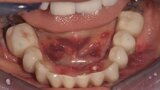

Natychmiastowa implantacja i zaopatrzenie protetyczne pacjentów z zaawansowaną chorobą przyzębia